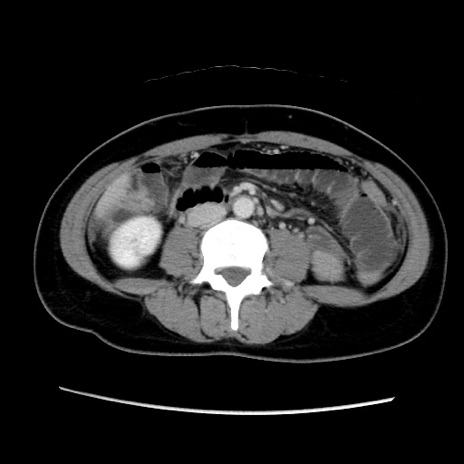

MRI(4日後)

【症例】40歳代女性

【主訴】上下腹部痛

【現病歴】2日目から下腹部痛あり。夜間は痛みで眠れなかった。昨日より上腹部痛と下痢が出現。臥位で痛みは軽快したため、休んでいた。本日になって臥位でも立位でも痛みが強くなってきたため救急要請。

【既往歴】子宮内膜症

【身体所見】部:平坦・軟、左上下腹部に圧痛あり、反跳痛あり。

【データ】WBC 21800、CRP 26.78